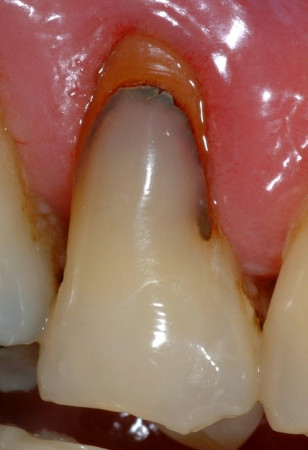

En ce qui concerne les verres hybrides, les seules données disponibles sont des études randomisées qui ont comparé ce matériau avec les résines composites dans les lésions non carieuses (Fig. 4).

Fig. 4a : Dans les études cliniques randomisées et contrôlées, les verres hybrides montrent des résultats prometteurs pour la restauration des lésions cervicales. a) Lésion cervicale non carieuse, avant traitement,